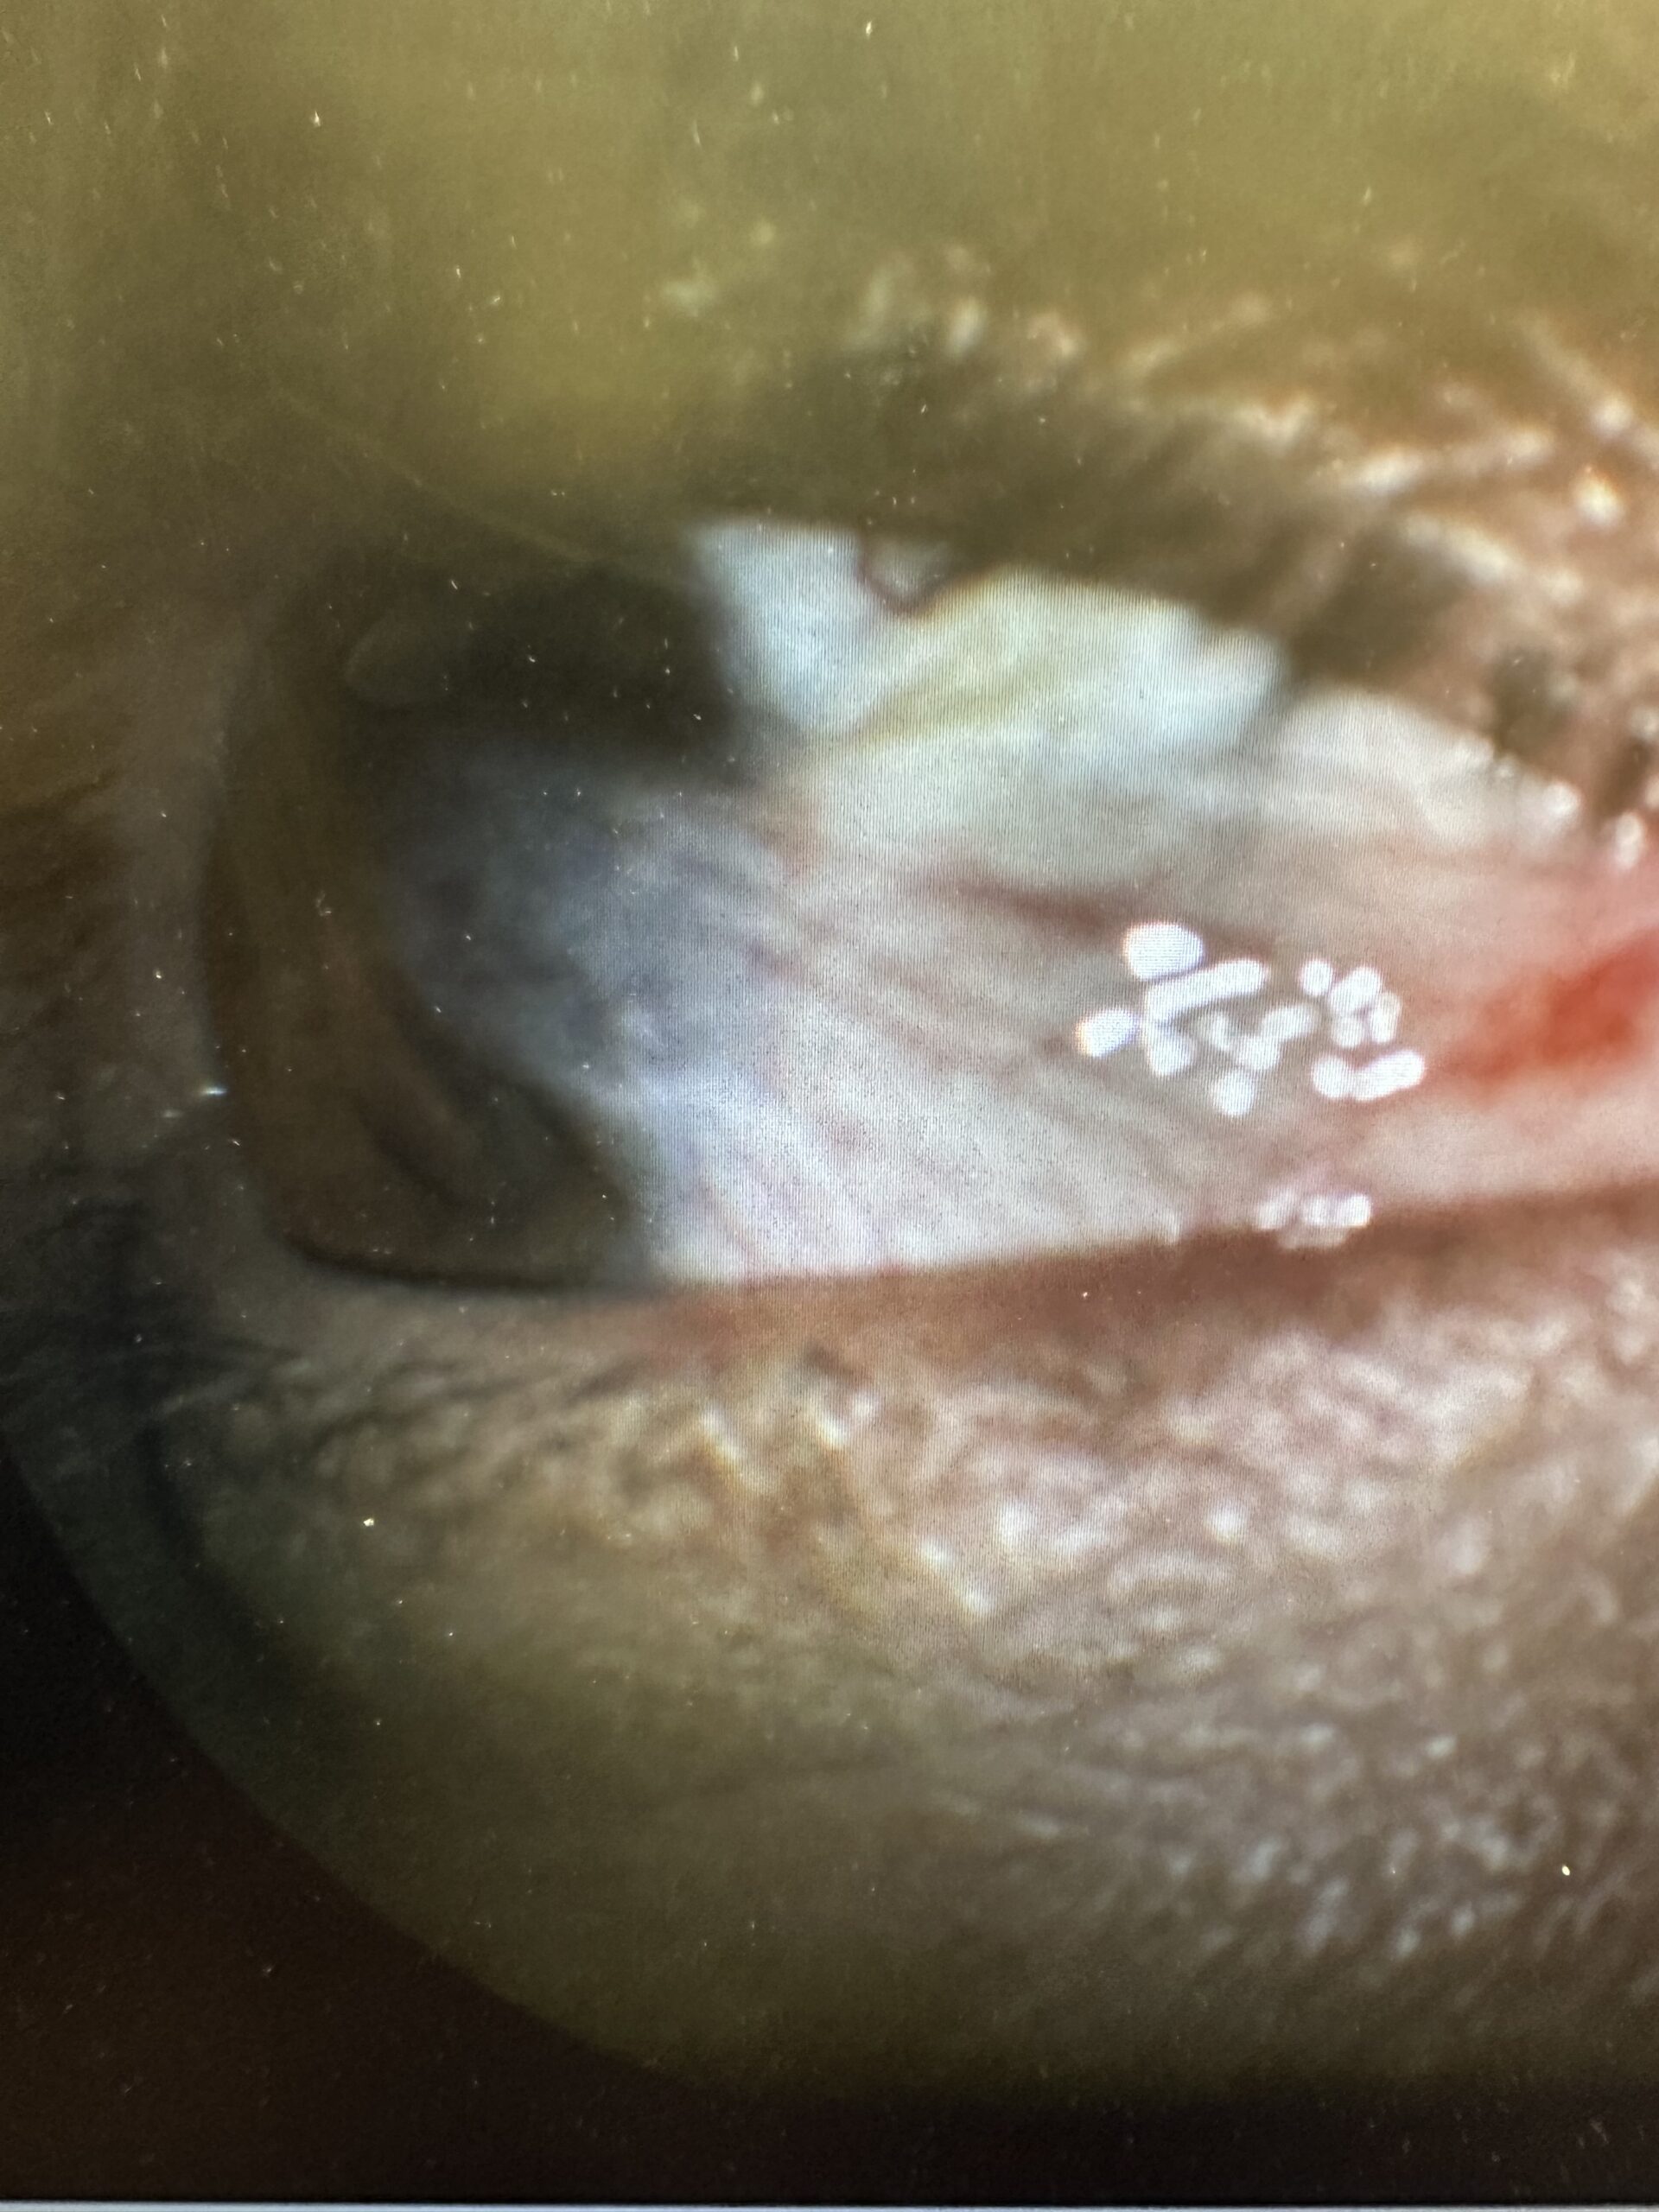

Neil Nichols, MD is a board certified ophthalmologist specializing in oculoplastic surgery. He engages in continuous education and professional development to stay up to date on the latest technological advances in all aspects of ophthalmic plastics, Oculofacial, and reconstructive surgery. In addition, Dr. Nichols continues to have clinical and research interests in Cornea and refractive surgery and has helped publish numerous professional research articles in the field of ophthalmology. He has evolved into one of the leading pterygium surgeons in the United States and has partnered with several medical device companies to offer his patients the latest technological advancements in grating materials and techniques. His high level of surgical skill and commitment to his craft assures his patients receive the most effective treatments along with optimal outcomes. Dr. Nichols sees patients in Amityville, Brooklyn, NYC 27th Street, Sayville, Brentwood, Port Jefferson, Bay Shore, and Hauppauge providing quality eye care across Long Island and New York City.